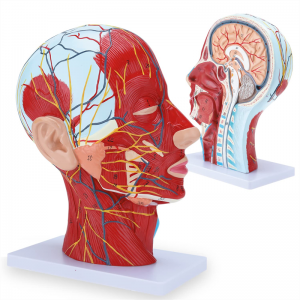

| Caracteristici | Modelul arată morfologia locală a laturilor interioare și exterioare ale secțiunii sagitale mediane a capului și a gâtului, precum și a structurilor vaselor de sânge și a nervilor și există 84 de părți care indică semne în total. |

【1: 1 LIFESIZE】 Secțiune mediană din 1: 1 Modelul mușchiului vascular neural superficial al capului mare și al gâtului natural (partea dreaptă). Manopera fină. Oferind o gamă completă de caracteristici anatomice.

【Caracteristici】 arată mușchii superficiali ai feței expuse; vasele de sânge superficiale și nervii feței & scalp; structurile interioare ale glandei parotide și ale tractului respirator superior; Structura de secțiune sagitală a coloanei vertebrale cervicale.

Modelul a arătat morfologia locală a secțiunilor sagitale mediale și laterale ale capului și gâtului și ale structurilor sale vasculare și nervoase, cu un total de 100 de indicatori de sit.

Acest model este un model natural de mușchi neurovascular superficial al capului și gâtului, 1 componentă, care arată detaliile capului drept și gâtului drept și secțiunea sagitală mediană, inclusiv mușchii superficiali expuși ai feței, vasele superficiale ale feței și scalpului, nervii și structura medială a glandei parotide și a tractului respirator superior și a structurii secțiunii sagitale a coloanei vertebrale cervicale